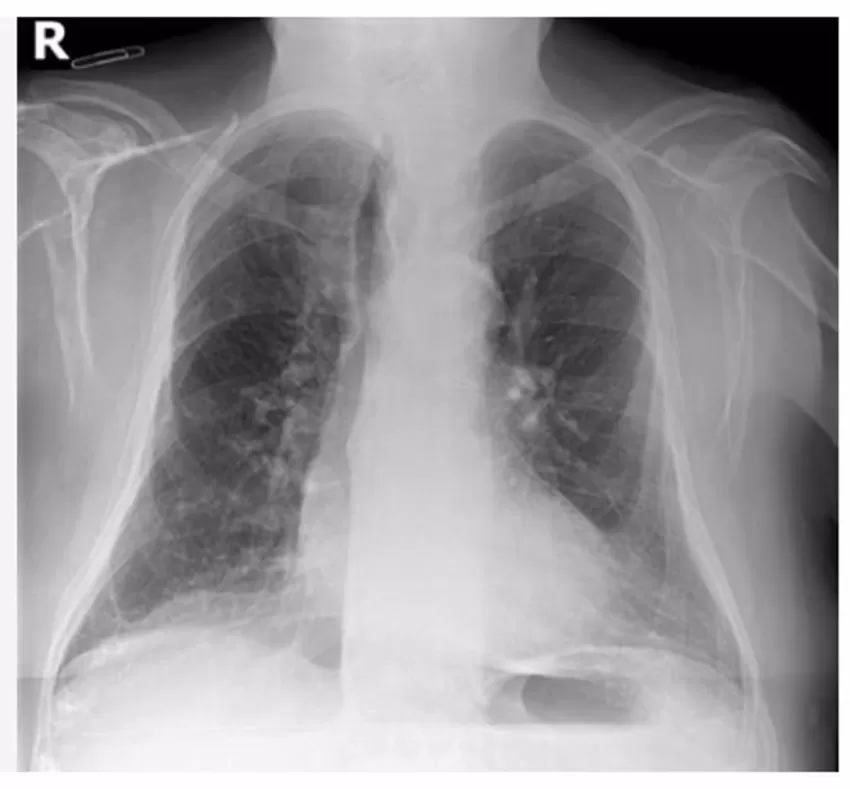

Personal científico de la Fundación para el Fomento de la Investigación Sanitaria y Biomédica de la Comunitat Valenciana (Fisabio), en colaboración con la Society for Imaging Informatics in Medicine (SIIM), ha convocado un 'challenge' o desafío científico a nivel internacional para la detección de Covid-19 en radiografías de tórax a través de Inteligencia Artificial (IA).

Los científicos han recopilado datos de radiografías torácicas de pacientes de la Comunitat Valenciana para generar modelos predictivos que utilicen la IA. Estos modelos son supervisados por radiólogos especialistas con el fin de detectar de forma temprana la neumonía por Covid-19 en pacientes con síntomas leves.

Actualmente se han compartido más de 12.456 sesiones de radiografías de tórax pertenecientes a unos 4.706 sujetos con patología Covid. Además, se cuenta con más de 6.012 sesiones de radiografías pertenecientes a unos 4.437 pacientes sanos o con distintas patologías provenientes de los sistemas de información sanitarios de la Conselleria de Sanidad Universal y Salud Pública, que serán la base con la que se iniciará este desafío científico.